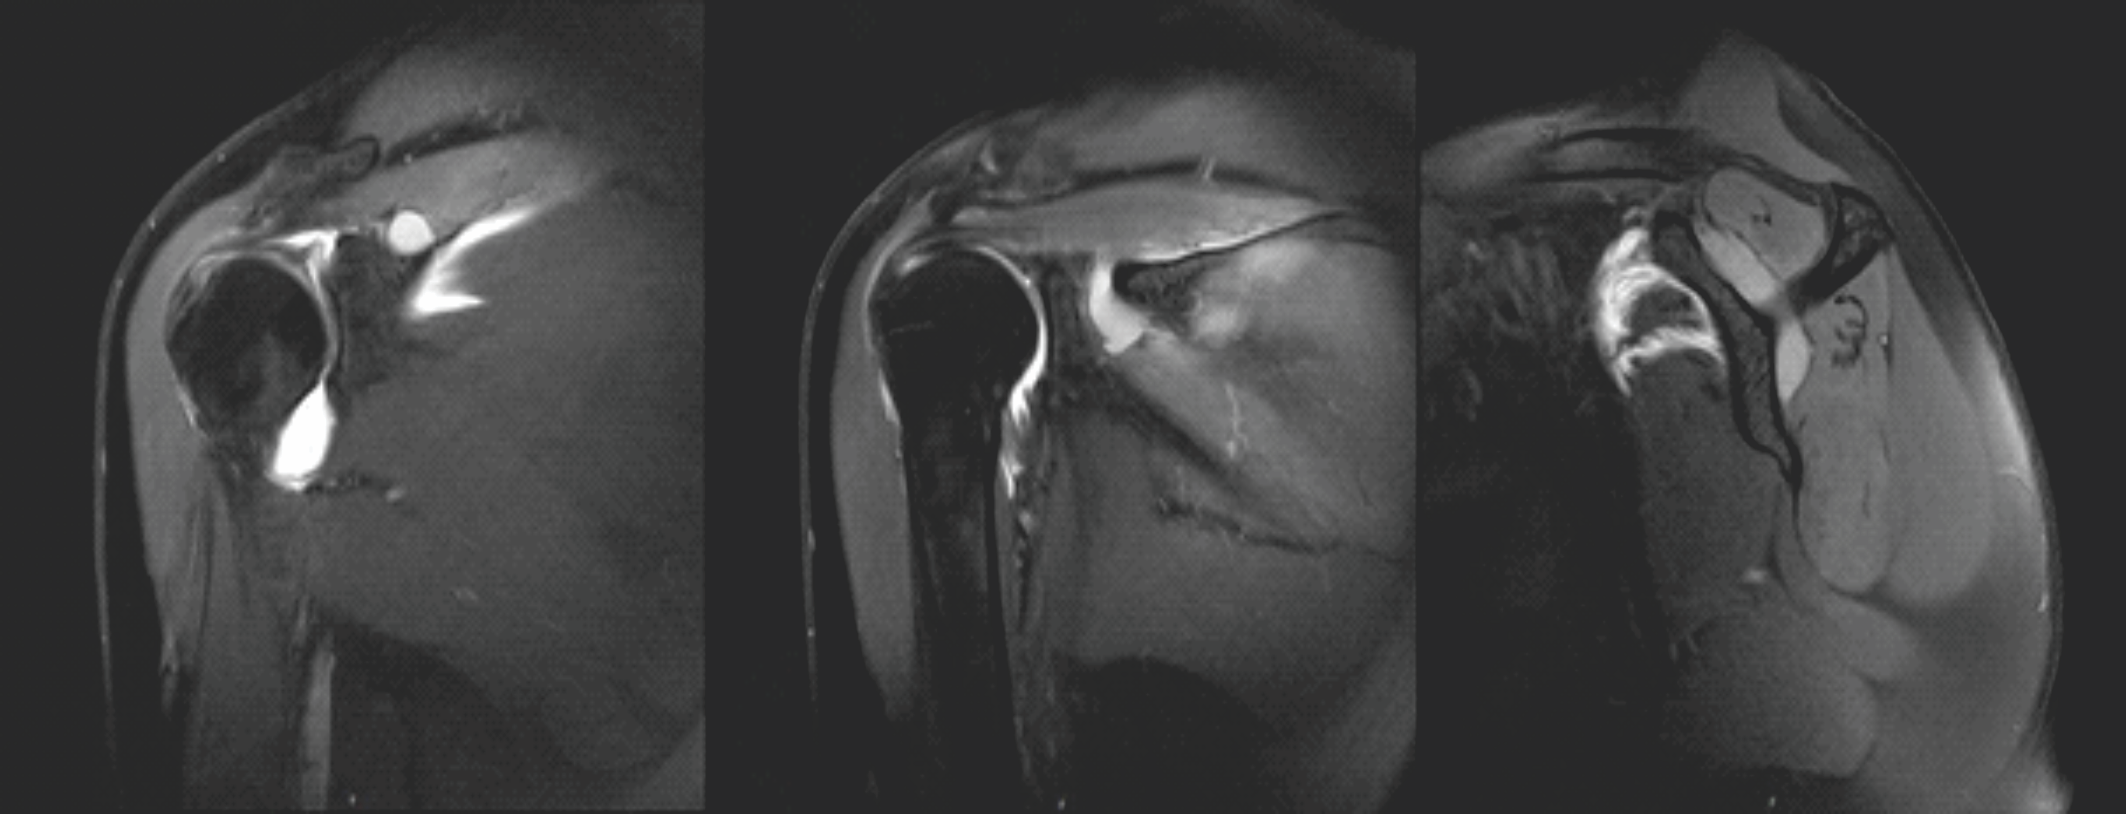

Figure 1: Magnetic resonance imaging of the right shoulder. This figure illustrates cystic formation at the suprascapular notch (left), the spinoglenoid notch (middle), and the tubular connection between the two (right).

A 63-year-old right-handed woman with no relevant medical history presented with a 6-month history of continuous dull right shoulder pain, aggravated by lying on the affected side and associated with nocturnal pain. She reported functional limitations in overhead activities. Analgesics included paracetamol, ibuprofen, and topical diclofenac. Her regular physical activities included walking and cycling. Examination showed normal biceps and triceps reflexes, intact sensation, negative Spurling’s test, and preserved cervical and cervicodorsal mobility with negative facet joint and foraminal compression tests. Increased tone was noted in the postural muscles, mainly in the upper trapezius. Shoulder assessment revealed painless passive external rotation and abduction-external rotation, but active external rotation strength was reduced to 4/5 on the Medical Research Council scale. Impingement signs and Jobe’s test were negative. Palpation over the suprascapular notch elicited tenderness. Ultrasound revealed a cystic lesion posterior to the glenoid. Arthro-MRI confirmed a cyst from the spinoglenoid to the suprascapular notch along the course of the SSN. No teres minor atrophy was observed. Additional findings included insertional tendinopathy of the supraspinatus and a superoposterior labral tear. The imaging appearance was consistent with an intraneural ganglion cyst. Electromyography (EMG) showed a right SSN lesion at or proximal to the supraspinatus muscle branch, consistent with a partial axonotmesis and associated with moderate-to-severe muscular involvement. The patient initially opted for a conservative approach with physiotherapy, ultrasound-guided aspiration, and intralesional glucocorticoid injection for symptomatic relief (Depo-Medrol 80 mg). Aspiration of the cyst was attempted. However, only 1 mL of the thick mucinous fluid could be retrieved. At 4 weeks, pain improved but there was persistent fatigue with overhead activity and weakness in both the supraspinatus and infraspinatus. Ultrasound showed a persistent anechoic, lobulated cyst (9.4 × 7.6 mm) in the suprascapular notch, with extension to the spinoglenoid (4.1 × 7.4 mm) notch, without hyperemia. Physiotherapy was continued, with follow-up planned in 2 months. Two months later, ultrasound showed enlargement at the suprascapular notch (11.4 × 9.3 mm) and a stable size at the spinoglenoid notch (4.0 × 7.3 mm) (Fig. 2). EMG revealed improved compound muscle action potential (CMAP) amplitude and recruitment in the supraspinatus, but decreased recruitment and denervation in the infraspinatus. A surgical indication was made for arthroscopic decompression of the cyst at both the suprascapular and spinoglenoid notches and treatment of the labral tear. Arthroscopy revealed a degenerative type IIB superior labrum anterior to posterior (SLAP) lesion, treated with biceps tenotomy and labral debridement, as repair was deemed infeasible. Cyst decompression exposed a well-defined synovial cyst wall surrounding the nerve. Incision released a wine-red mucinous fluid, and the wall was carefully debrided to achieve complete decompression (Fig. 1)